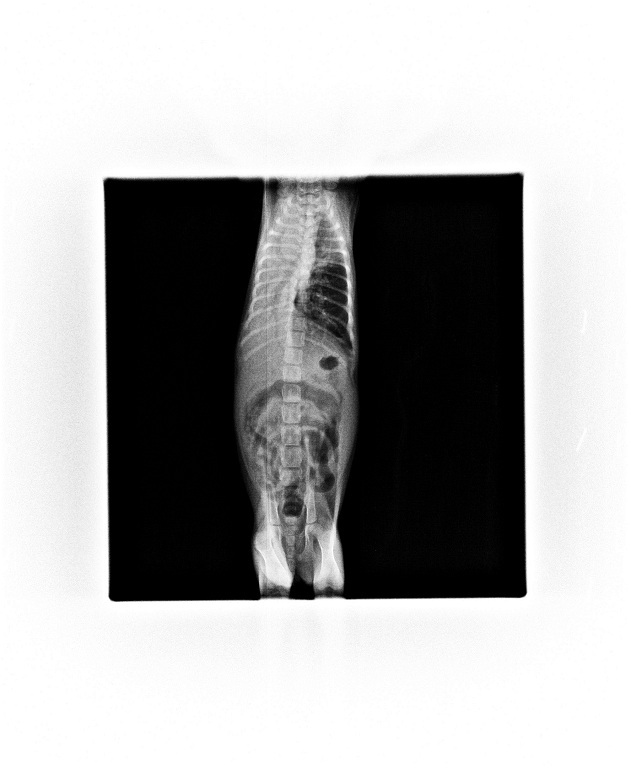

順子這天拍X光和掃肺部超音波,

可以看到肺部都是花花白白的,

且血檢白血球6萬1發炎情況嚴重,

醫生說是嚴重肺炎需住院吸氧,

且還是不時會咳嗽、肺部照X光還是有點花,

也需要經常拍X光照片檢視小順子肺部的發炎狀況,